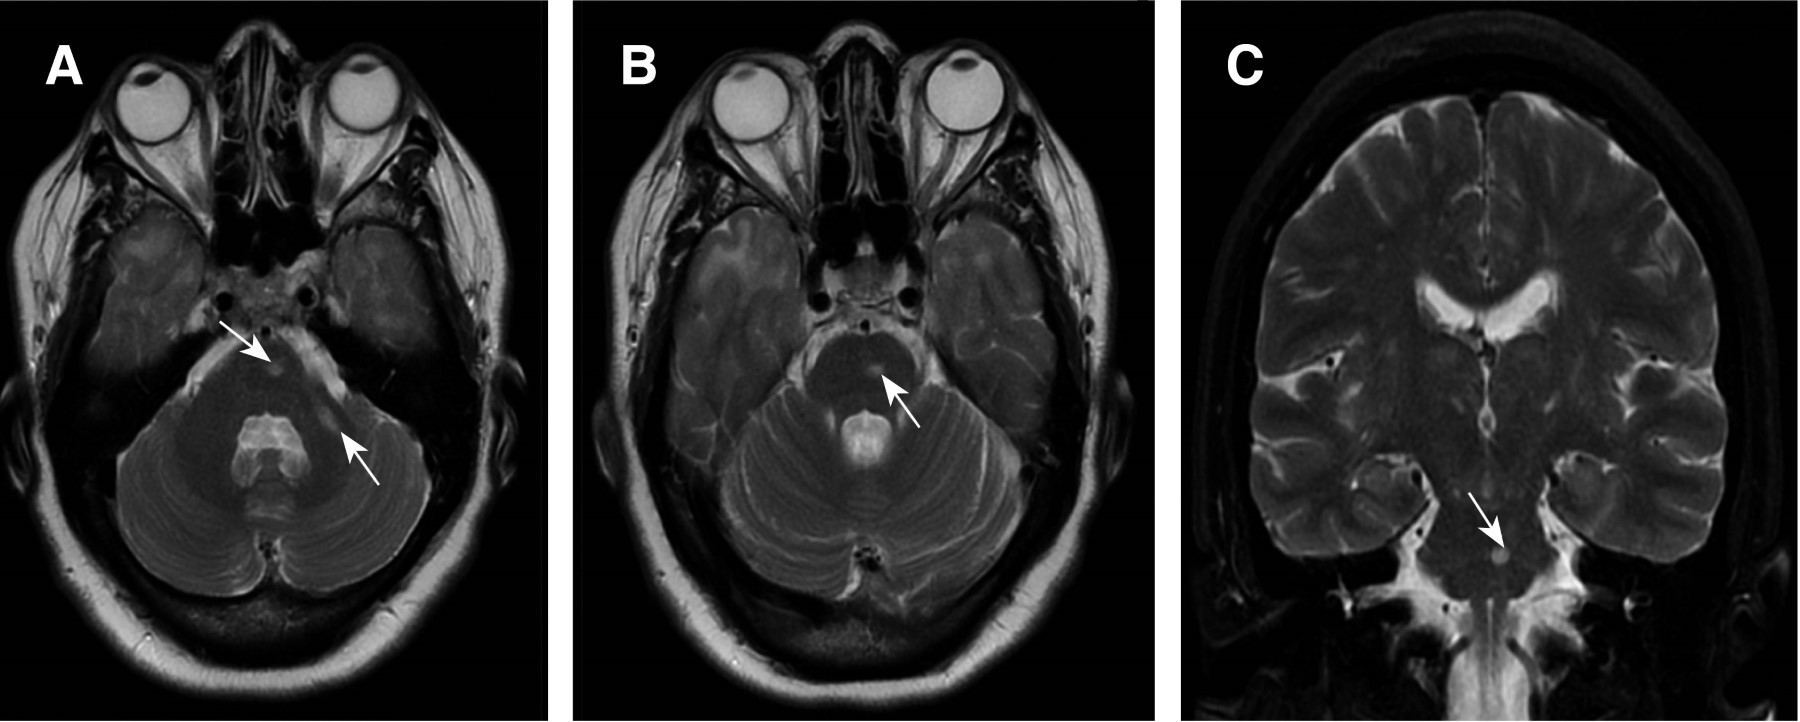

A los 46 años presentó súbitamente aumento de la debilidad hemicorporal derecha y disartria, se realizó IRM cerebral encontrando en secuencia T2 lesiones hiperintensas en sustancia blanca a nivel del bulbo, puente y pedúnculo cerebeloso inferior izquierdo (Figura 1) y en secuencia fluid-attenuated inversion recovery (FLAIR) lesiones hiperintensas en sustancia blanca superficial y profunda en ambos polos temporales, parietal y frontal bilateral, periventriculares, periatriales, adyacentes a la ínsula y en cuerpo calloso (Figura 2), sugestivos de EVC isquémico en territorio de la arteria cerebral media izquierda en su segmento M2. Los exámenes de laboratorio y gabinete, incluyendo proteína C y S, antitrombina III, factor V de Leyden, angiotomografía de troncos supraaórticos, electrocardiograma, estudio Holter, ecocardiograma, todos dentro de la normalidad. Se realizó estudio genético, el cual reportó mutación del gen NOTCH3 c.544C>T (pL151P). Se inició tratamiento de profilaxis secundaria con atorvastatina y ácido acetilsalicílico e ingresó al programa de rehabilitación física.

Figura 1